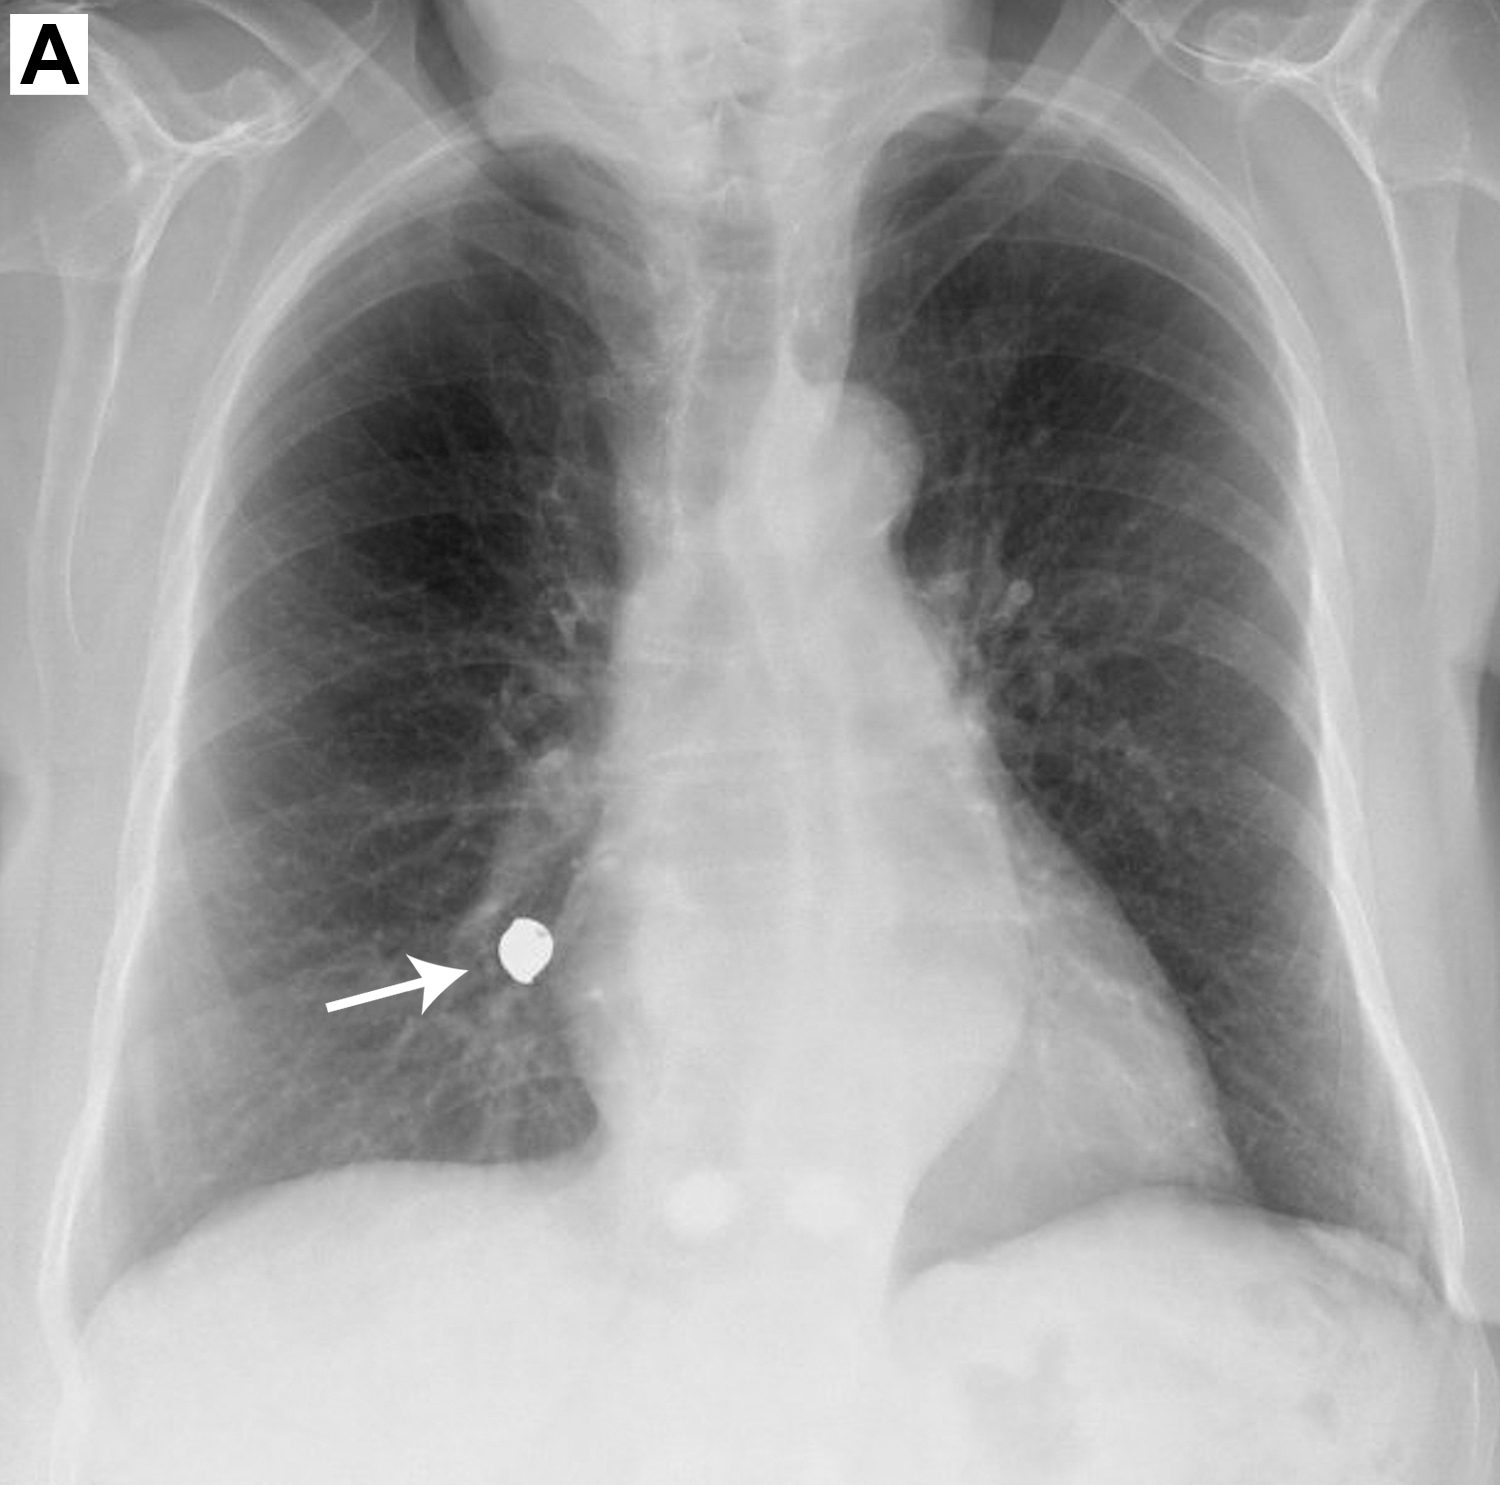

An 86-year-old woman presented to the pulmonology department following a 4-month history of a progressive nonproductive cough, wheezing, and exertional dyspnea. A plain-film chest radiograph demonstrated a foreign body in the lower lobe of her right lung (image A). Symptoms began 1 week after a tooth extraction, during which a gold crown on an adjacent tooth was dislodged and presumably ingested. Chest computed tomography confirmed a foreign body in the basal segment of the right lower lobe. Subsequent flexible bronchoscopy revealed a metallic-appearing object in the right bronchus intermedius (image B), which was successfully extracted via bronchoscopy using a basket instrument for renal stones.

Tracheobronchial foreign body aspiration is a rare occurrence among adults.1,2 Clinical manifestations of distal airway obstruction include chronic cough, fever, hemoptysis, chest pain, and wheezing, which can be further complicated by postobstructive pneumonia and atelectasis.1,3 Flexible bronchoscopy serves as a diagnostic and therapeutic modality in the management of lower airway obstruction.1,4